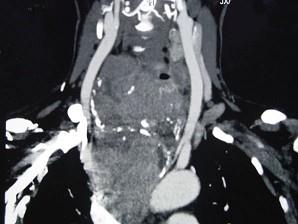

问题 女性,48岁,颈部包块3年,近来胸闷、憋气、胸痛,CT扫描如图,请选择正确的描述和答案 ( )

选项 A、胸骨后甲状腺肿是指甲状腺50%位于胸骨后 B、胸骨后甲状腺肿是指甲状腺60%位于胸骨后 C、考虑为血管瘤 D、考虑为双侧甲状腺肿大 E、考虑为胸骨后甲状腺肿

答案 AE